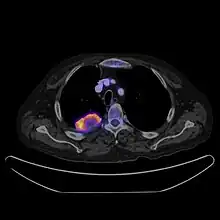

PET CT

Positron emission tomography–computed tomography is a hybrid CT modality which combines, in a single gantry, a positron emission tomography (PET) scanner and an x-ray computed tomography (CT) scanner, to acquire sequential images from both devices in the same session, which are combined into a single superposed (co-registered) image. Thus, functional imaging obtained by PET, which depicts the spatial distribution of metabolic or biochemical activity in the body can be more precisely aligned or correlated with anatomic imaging obtained by CT scanning.[22]

PET-CT gives both anatomical and functional details of an organ under examination and is helpful in detecting different type of cancers.[23][24]